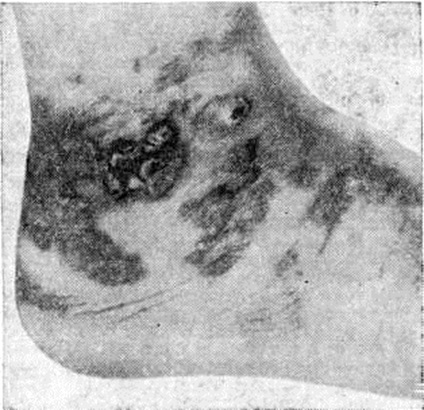

Рис. 2.

Микроскопическая картина саркомы Капоши: в опухоли — участки грануляционной ткани различной степени зрелости (указаны стрелками); × 115.

Микроскопически в опухоли всегда обнаруживают большое количество кровеносных сосудов, чаще капиллярного типа. Эндотелиальные клетки сочные, набухшие, местами сгруппированы в небольшие тяжи; вокруг сосудов — неспецифический воспалительный инфильтрат, состоящий из лимфоцитов, гистиоцитов, плазматических клеток и другие. На отдельных участках эндотелиальные клетки с явлениями атипизма и единичными фигурами деления ядер; встречаются разрастания веретенообразных клеток, среди которых видны сосудистые щели. В пределах опухоли определяются также участки грануляционной ткани различной степени зрелости (рисунок 2), некрозы, массивные кровоизлияния и скопления гемосидерина. Характерны связанные с сосудами пучки веретенообразных клеток, не полностью сформированные сосуды, нарушение целостности стенок и кровоизлияния вокруг сосудов (рисунок 3). В опухоли обнаруживают все указанные структуры в различных сочетаниях, что и создаёт разнообразие гистологический картины. Выделяют воспалительно-гранулематозную и позднюю опухолевую стадии развития Капоши саркома множественная геморрагическая.

В воспалительно-гранулематозной стадии отмечают большое количество расширенных кровеносных сосудов в дерме, эндотелий их набухший, сочный; вокруг сосудов — инфильтрация из лимфоидных элементов, плазматических клеток, гистиоцитов, фибробластов.

Характерной гистологический особенностью является наличие в соединительной ткани эндотелиальных клеток, из которых образуются новые сосуды, а также эритроцитов вне просвета сосудов и увеличение содержания гемосидерина. В ранних стадиях гистологический картина не всегда характерна: Капоши саркома множественная геморрагическая трудно дифференцировать от ангиомы и богатой сосудами грануляционной ткани. Правильному диагнозу помогает обнаружение в гранулематозной ткани экстравазатов и гемосидерина.